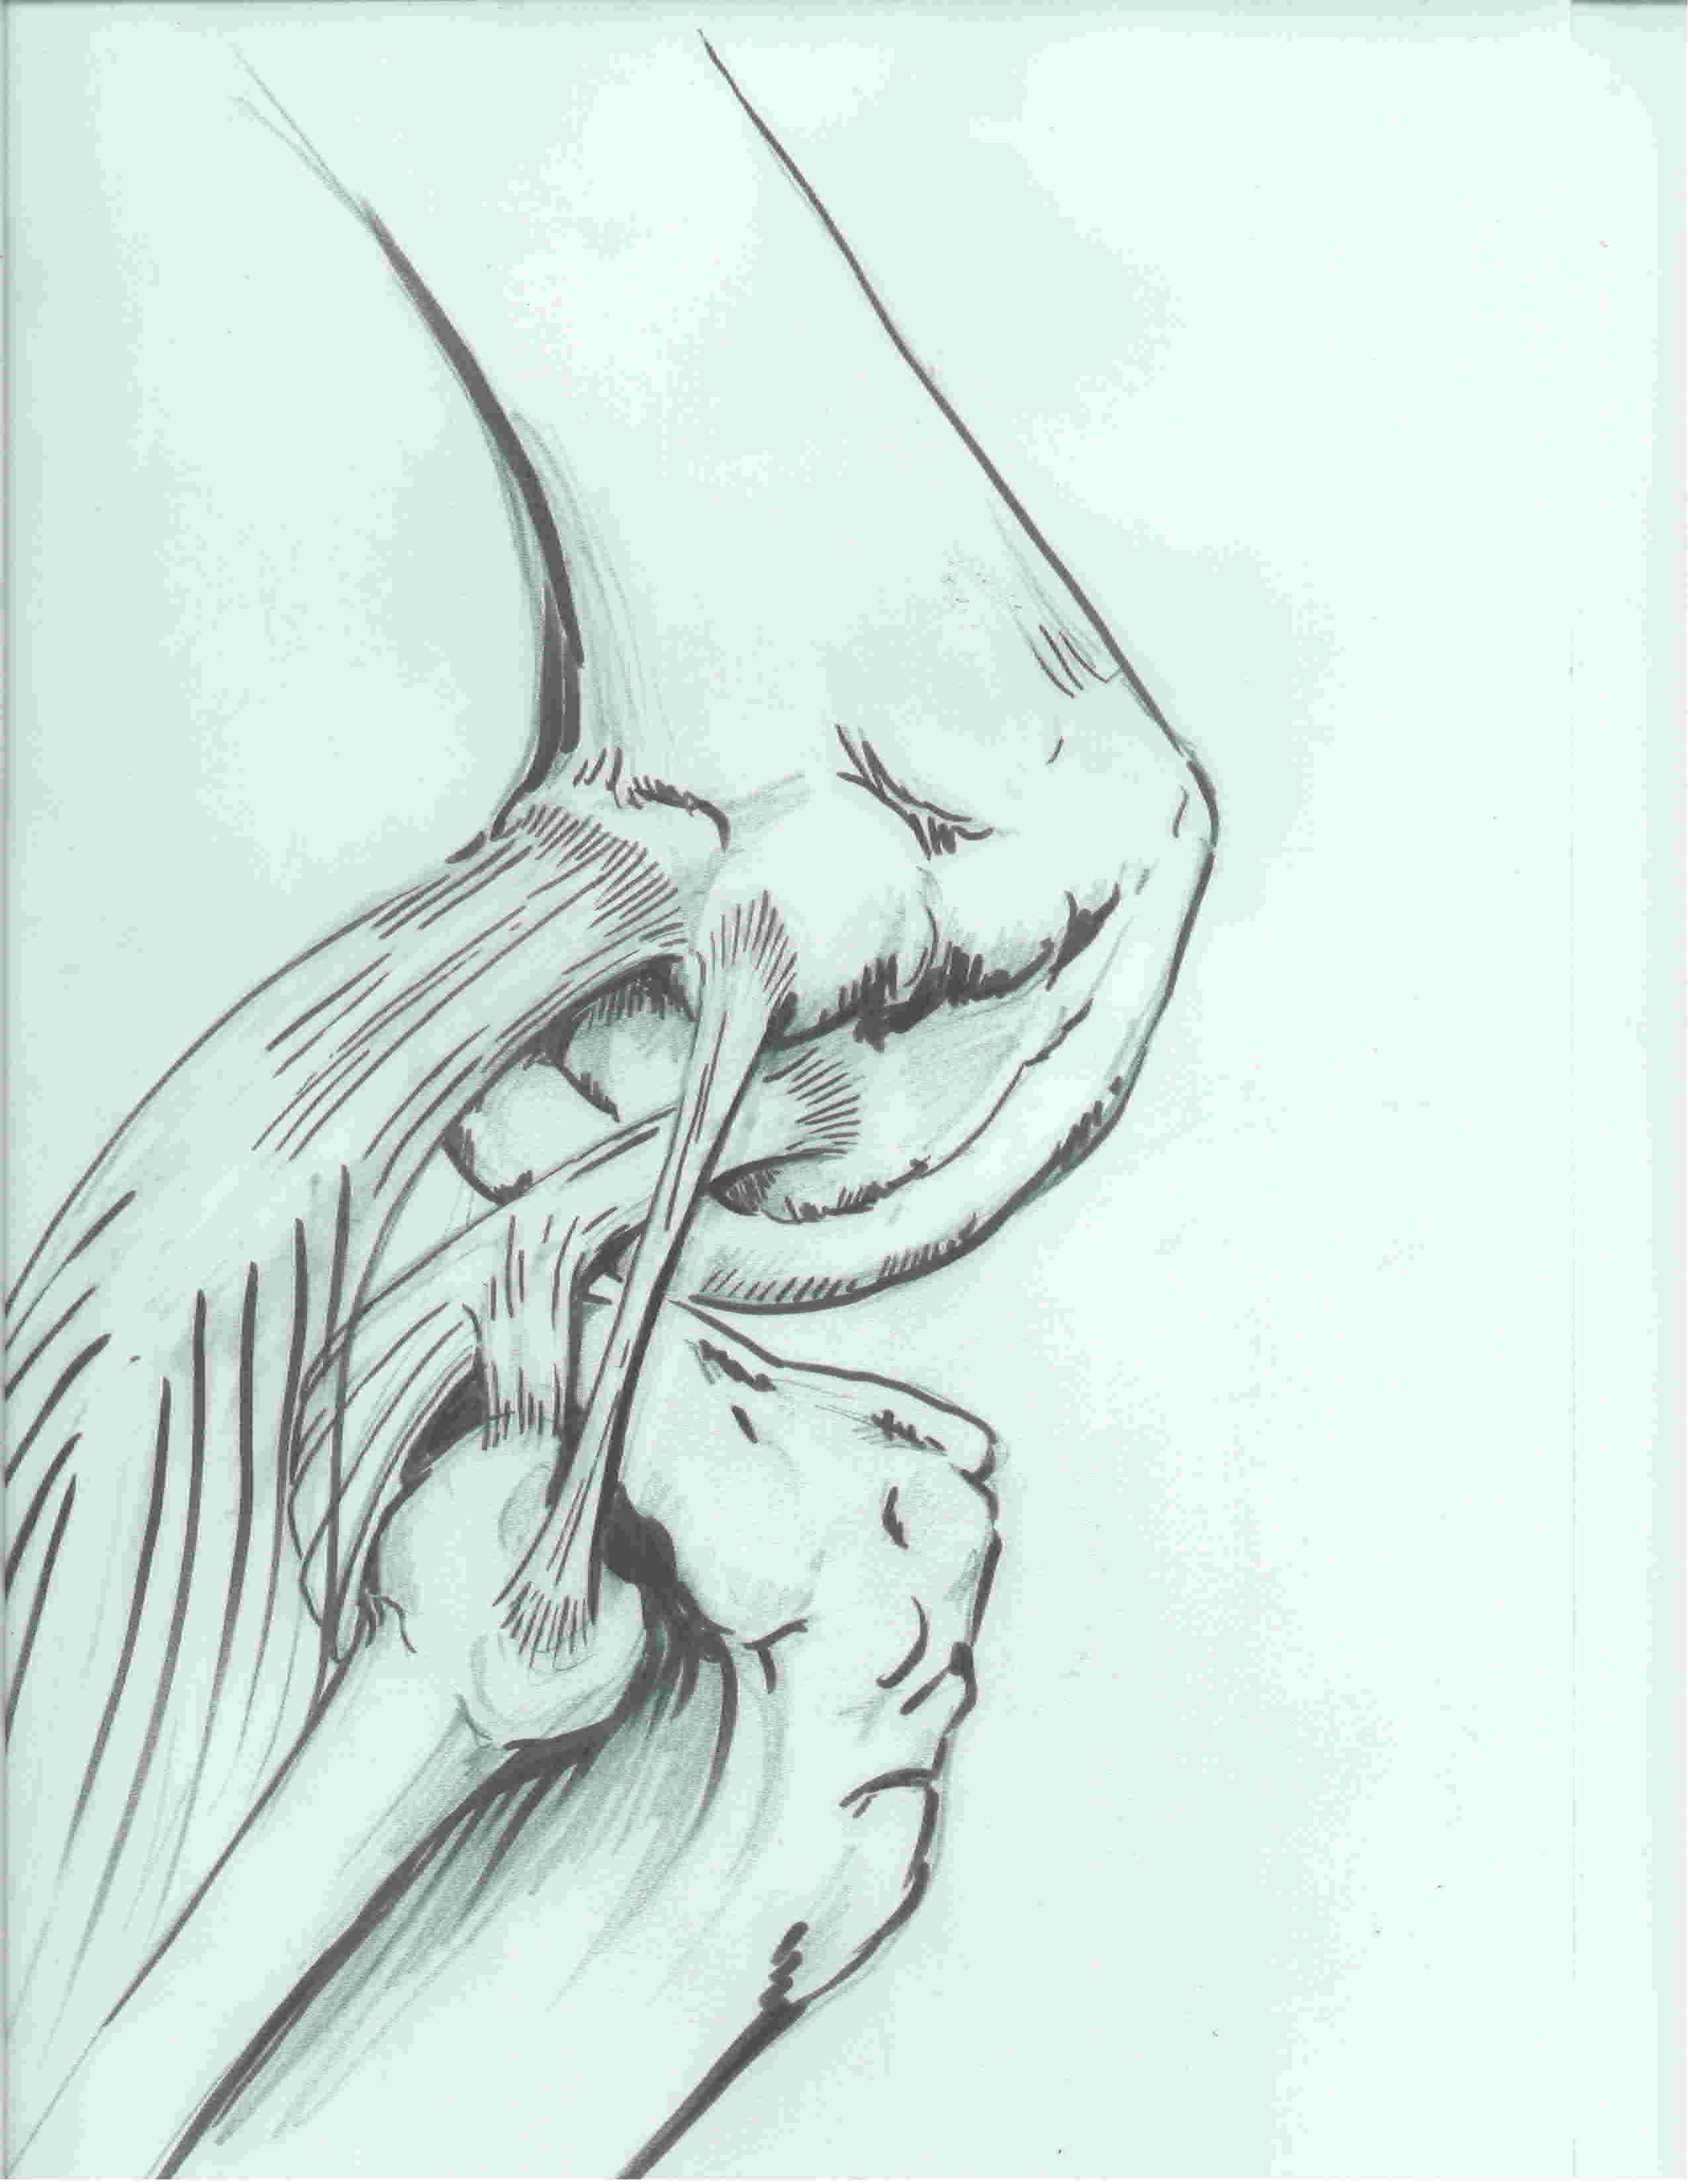

2. Popliteus tendon

Origin

- posteromedial tibial

- becomes tendon at lateral one third of the popliteal fossa

Insertion

- tendon passes through capsule and hiatus in coronary ligament of lateral meniscus

- runs around lateral femoral condyle

- passes deep to LCL

- inserts into most anterior aspect of the popliteus sulcus

- always anterior and distal to LCL

- average 18.5 mm between LCL and popliteus femoral insertion

3. Popliteofibular ligament

Origin

- musculotendinous junction of the popliteus tendon

Insertion

- fibular styloid

Action

- acts as check rein to popliteus

- resists external rotation